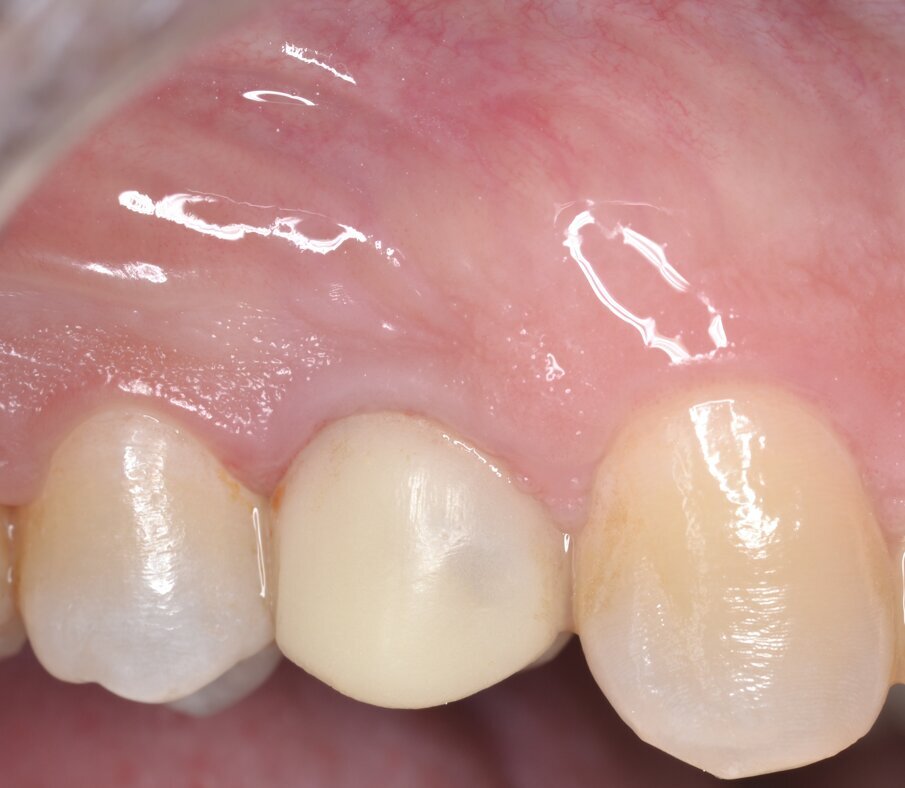

Il primo follow-up effettuato a 14 giorni mostra un eccellente stato di salute dei tessuti duri e molli; è importante sottolineare come il profilo di emergenza della protesi provvisoria, opportunamente lucidato al momento della protesizzazione, guiderà i tessuti molli durante tutto il periodo di guarigione (Fig. 19). Le immagini del secondo follow-up a 4 mesi indicano una condizione di sostanziale salute e stabilità dei tessuti peri-implantari duri e molli: questo consente di programmare la successiva fase di finalizzazione protesica (Fig. 20).

Fig. 20 - Aspetto dei tessuti molli al termine della guarigione (4 mesi).